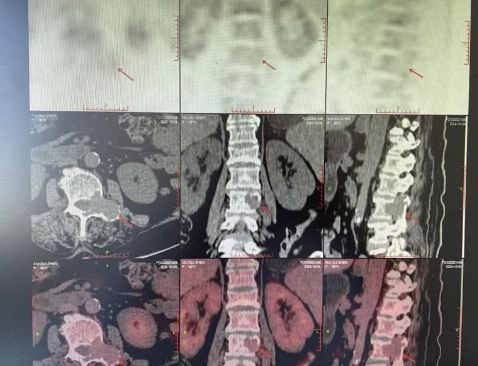

雖然醫(yī)生一直安慰,但劉阿姨平靜的生活被擊得粉碎,本是與老伴安享晚年的時候,現(xiàn)卻臥床不起,劉阿姨心中有著說不出的酸楚。CT影像上,骨骼像被蟲蛀了一般的空洞清晰可見,這些空洞無聲地訴說著疾病的殘酷。